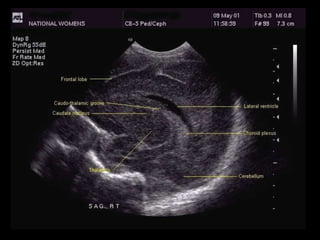

Angled Parasagittal View:

The shape of the lateral ventricle is the key landmark for this view.

The caudate nucleus lies below the floor of the frontal horn of the lateral ventricle; the

thalamus lies behind and below it.

The occipital horn of the lateral ventricle is filled with choroid plexus.

The choroid tucks up in the caudothalamic groove in the floor of the lateral ventricle and may be

echogenic.

Angled Parasagittal View: Theshape of the lateral ventricle is the key landmark for this view. The caudate nucleus lies below the floor of the frontal horn of the lateral ventricle; the thalamus lies behind and below it. The occipital horn of the lateral ventricle is filled with choroid plexus. The choroid tucks up in the caudothalamic groove in the floor of the lateral ventricle and may be echogenic.